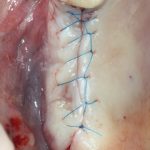

Простой синуслифтинг. Часть I.